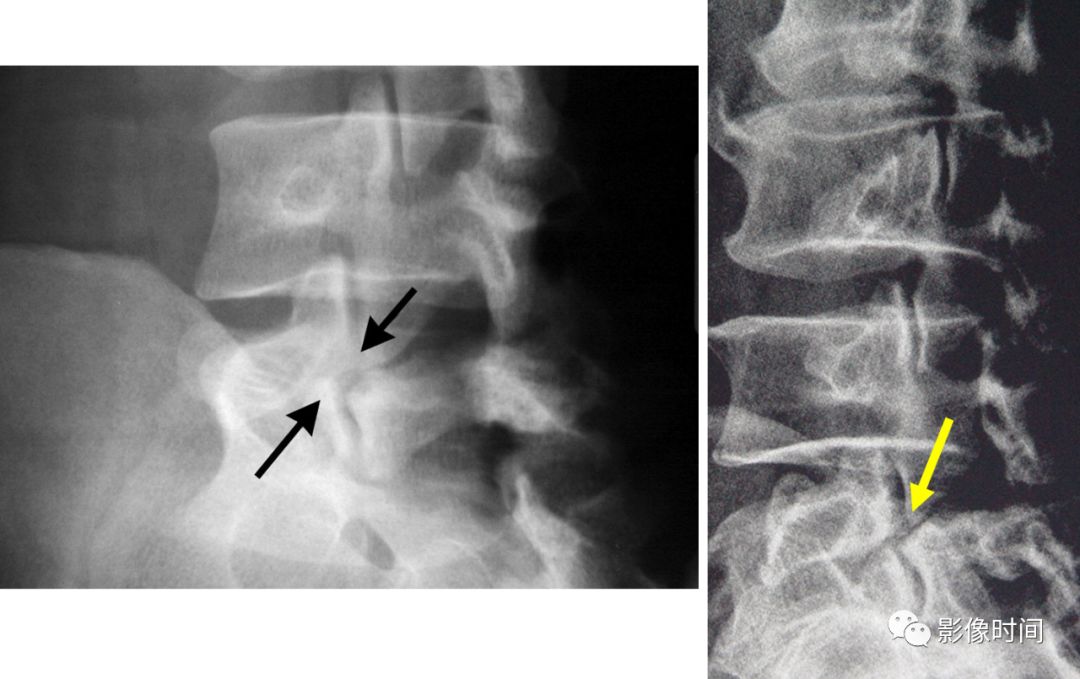

26夹心蛋糕征与橄榄球衫椎

前言:夹心蛋糕及橄榄球衫椎均用于描述椎体,上下终板区域带状密度增高,而中心区域密度相对低,高低密度区间杂。部分同道可能会混用,但两者有所不同,查询国内外书籍、文献及网页,总结如下:中文书籍中的所谓「夹心蛋糕征」,主要用于描述石骨症(也称骨硬化症),与英文「Sandwich vertebral body」(三明治椎体)对应,而橄榄球衫椎(Rugger-jersey spine)主要用于描述甲状旁腺功能亢进(原发及继发),国内主要用于描述肾性骨病,继发甲状旁腺功能亢进。

两者表现类似,区别在于三明治椎硬化带密度更高,边界更清晰,而橄榄球衫椎硬化带边界不够清楚,也没有那么致密(注:确实有混用情况,但大部分如上所说)。

典型病例

病例 1,石骨症。腰椎正侧位片示腰椎椎体上、下终板区域显著硬化,而中央区密度较低,呈夹心蛋糕征/三明治椎体。

病例 2,69 岁女性,肾性骨病。视野内诸骨密度不均匀增高,骨小梁模糊。腰椎椎体上下终板区域密度增高,中心区域密度较低,边界不清,呈「橄榄球衫椎」表现。